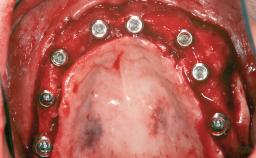

Guided Bone Regeneration (GBR) with a Particulated Autologous Graft and a ePTFE-Reinforced Membrane for Vertical Augmentation of a Single-Tooth Edentulous Space in the Esthetic Zone

Bone Augmentation Staged|Vertical

Augmentation Materials Autogenous chips|Membrane